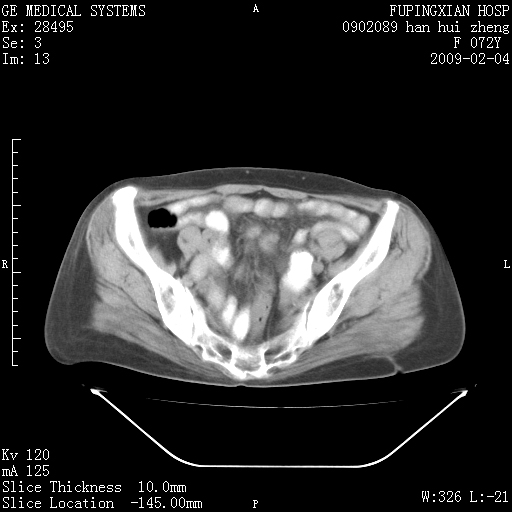

标题: CT17930:F72Y,右腹部包块5日,脐右扪及一包块,触痛。 [打印本页]

标题: CT17930:F72Y,右腹部包块5日,脐右扪及一包块,触痛。

胆囊增大,虽然内壁光滑,但囊壁不均匀性增厚,胆囊窝积液,所以首先考虑胆囊炎,但并不能排除胆囊癌的可能。诊断胆囊癌的依据是:胆囊壁呈不均匀性明显增厚,部分层面胆囊与肝脏界限不清。